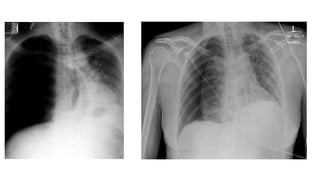

The document presents a chest X-ray examination summary by Ninian Peckitt, detailing various respiratory conditions including tracheal deviation, pleural effusions, and lung collapses. Findings suggest thoracic trauma and hyperinflation in the lungs. Additionally, it includes links to medical products and their pricing.